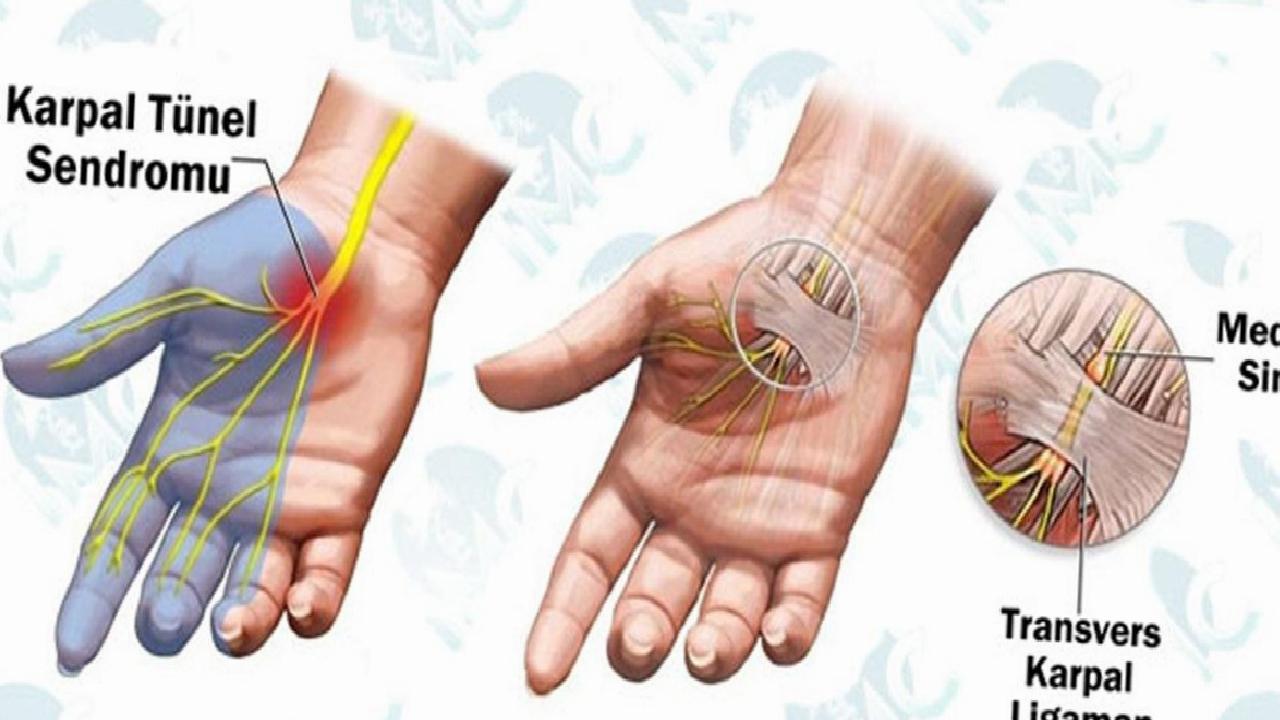

Karpal tünel sendromu; el bileğinden geçen sinirin (median adı veriliyor), ‘karpal tünel’ adı verilen kanalda sıkışması sonucu oluşan hastalıktır. Karpal Tünel, bilek seviyesinde ve üst kısmında kalın bir yapı ile kaplıdır. Bu kanalın içerisinde parmakların hareketini sağlayan tendonlar ile median sinir yer alır. Median sinir, parmakların (baş, işaret, orta ve yüzük) hissetmesini ve bazı hareketleri gerçekleştirmesini sağlar. Sinirin bu kanal içerisindeyken baskı altında kalması karpal tünel sendromunu ortaya çıkarır.

Genel vaka tablosunda küçük parmak haricinde diğer bütün parmaklar etkilendiği gözlemlenmiştir. Bazı vakalarda parmaklarda elektrik çarpması gibi bir his tasvir edilmiştir.